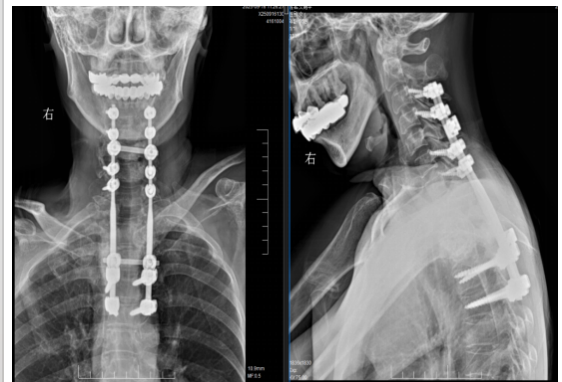

危急时刻,在朋友的建议下,艾女士辗转来到长沙市第一医院脊柱外科。入院检查结果令人揪心:8个椎体不同程度被掏空,最严重的胸1椎体被细菌啃掉90%(图1)、颈部巨大脓肿并流到椎管内压迫脊髓导致双下肢瘫痪(图2),肩部也有巨大的脓包(图2)、重度贫血、严重营养不良。若艾女士的病情无法及时控制,必将危及生命。

图1

为挽救患者神经功能,抢救患者生命,向伟能迅速组织多学科会诊,为患者量身定制个性化治疗方案:标准四联抗结核治疗、急诊一期颈椎前后路联合病灶清除植骨内固定手术。经过紧急而周密的准备,向伟能团队为艾女士实施了颈椎后路病灶清除椎管减压融合内固定术和颈椎前路病灶清除植骨融合术(图3)。历时6小时,手术团队成功将“蛀骨”病灶一网打尽,并用自体骨填补骨缺损,筑牢脊柱“支撑系统”。得益于成熟的MDT围手术期管理模式,该患者在6小时内顺利完成涵盖9个椎体的融合手术,以及后路联合前路的颈椎病灶清除术,术后患者情况稳定,直接被送返至普通病房,无需转入ICU监护。

图3